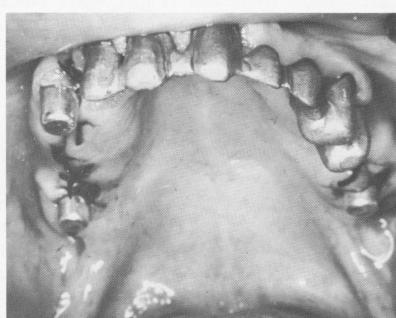

Fig. 11-80. The aluminum shells trimmed and placed over the implant posts with soft compound.